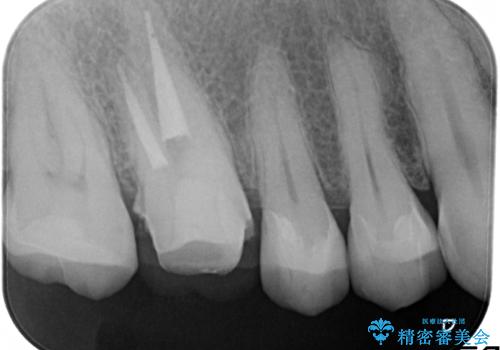

金属だらけの奥歯 根管治療のやり直しとセラミック化

- 神経のある歯を先にセラミック修復し、その後根管治療のやり直しを行う

→最終的にクラウンを製作し、きれいな奥歯を獲得する

インレー(詰め物)は、神経を保存したまま上部を丁寧にやり替えます。

神経の無い歯のクラウン(かぶせ物)は、根管治療を顕微鏡下でしっかりとやり直し、その後に土台の築造とかぶせ物の製作を行うことで今後問題が生じる可能性を可及的に低くできます。